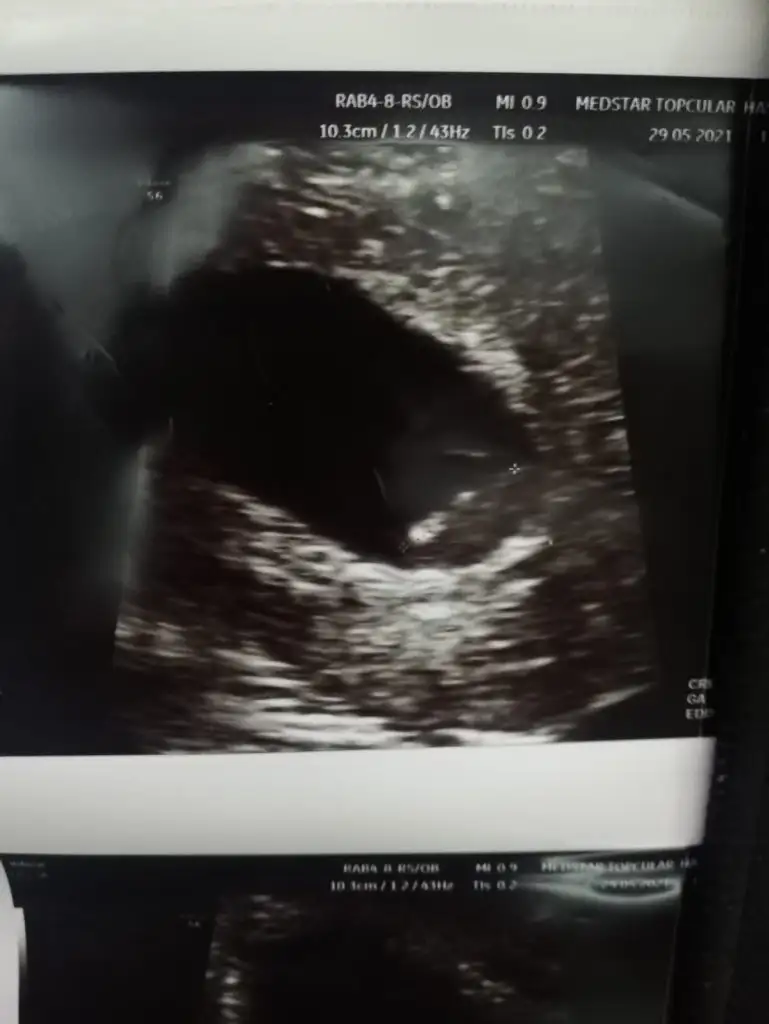

Ya çok güzel bir sayfa🤗 Benimkini de yorumlar mısınız kızlar ? Vajinal ultrason ikisi de. Haftaları yazıyor resme tıklayınca.

Eklentiler

• 7+3.webp

7+3.webp

30,9 KB · Görüntüleme: 74

• 8+3.webp

8+3.webp

28 KB · Görüntüleme: 88